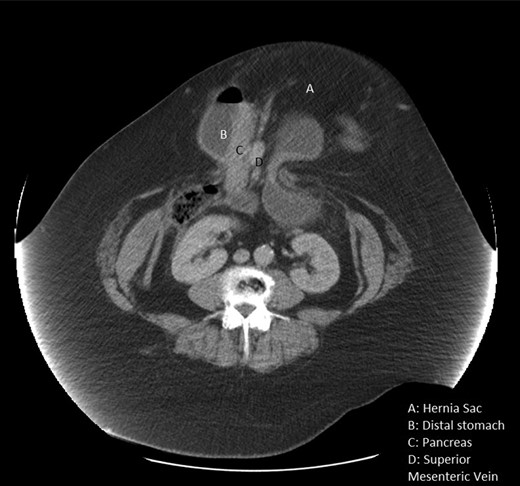

A computed tomography (CT) scan showed a large abdominal hernia containing loops of small bowel, sigmoid colon and transverse colon. In addition, the gastro-duodenal junction was in the sac pulling with it part of the posterior wall of the stomach, second part of the duodenum and the head of the pancreas (Fig. 1). The sigmoid colon had diverticular disease with evidence of perforation contained within the hernia sac.